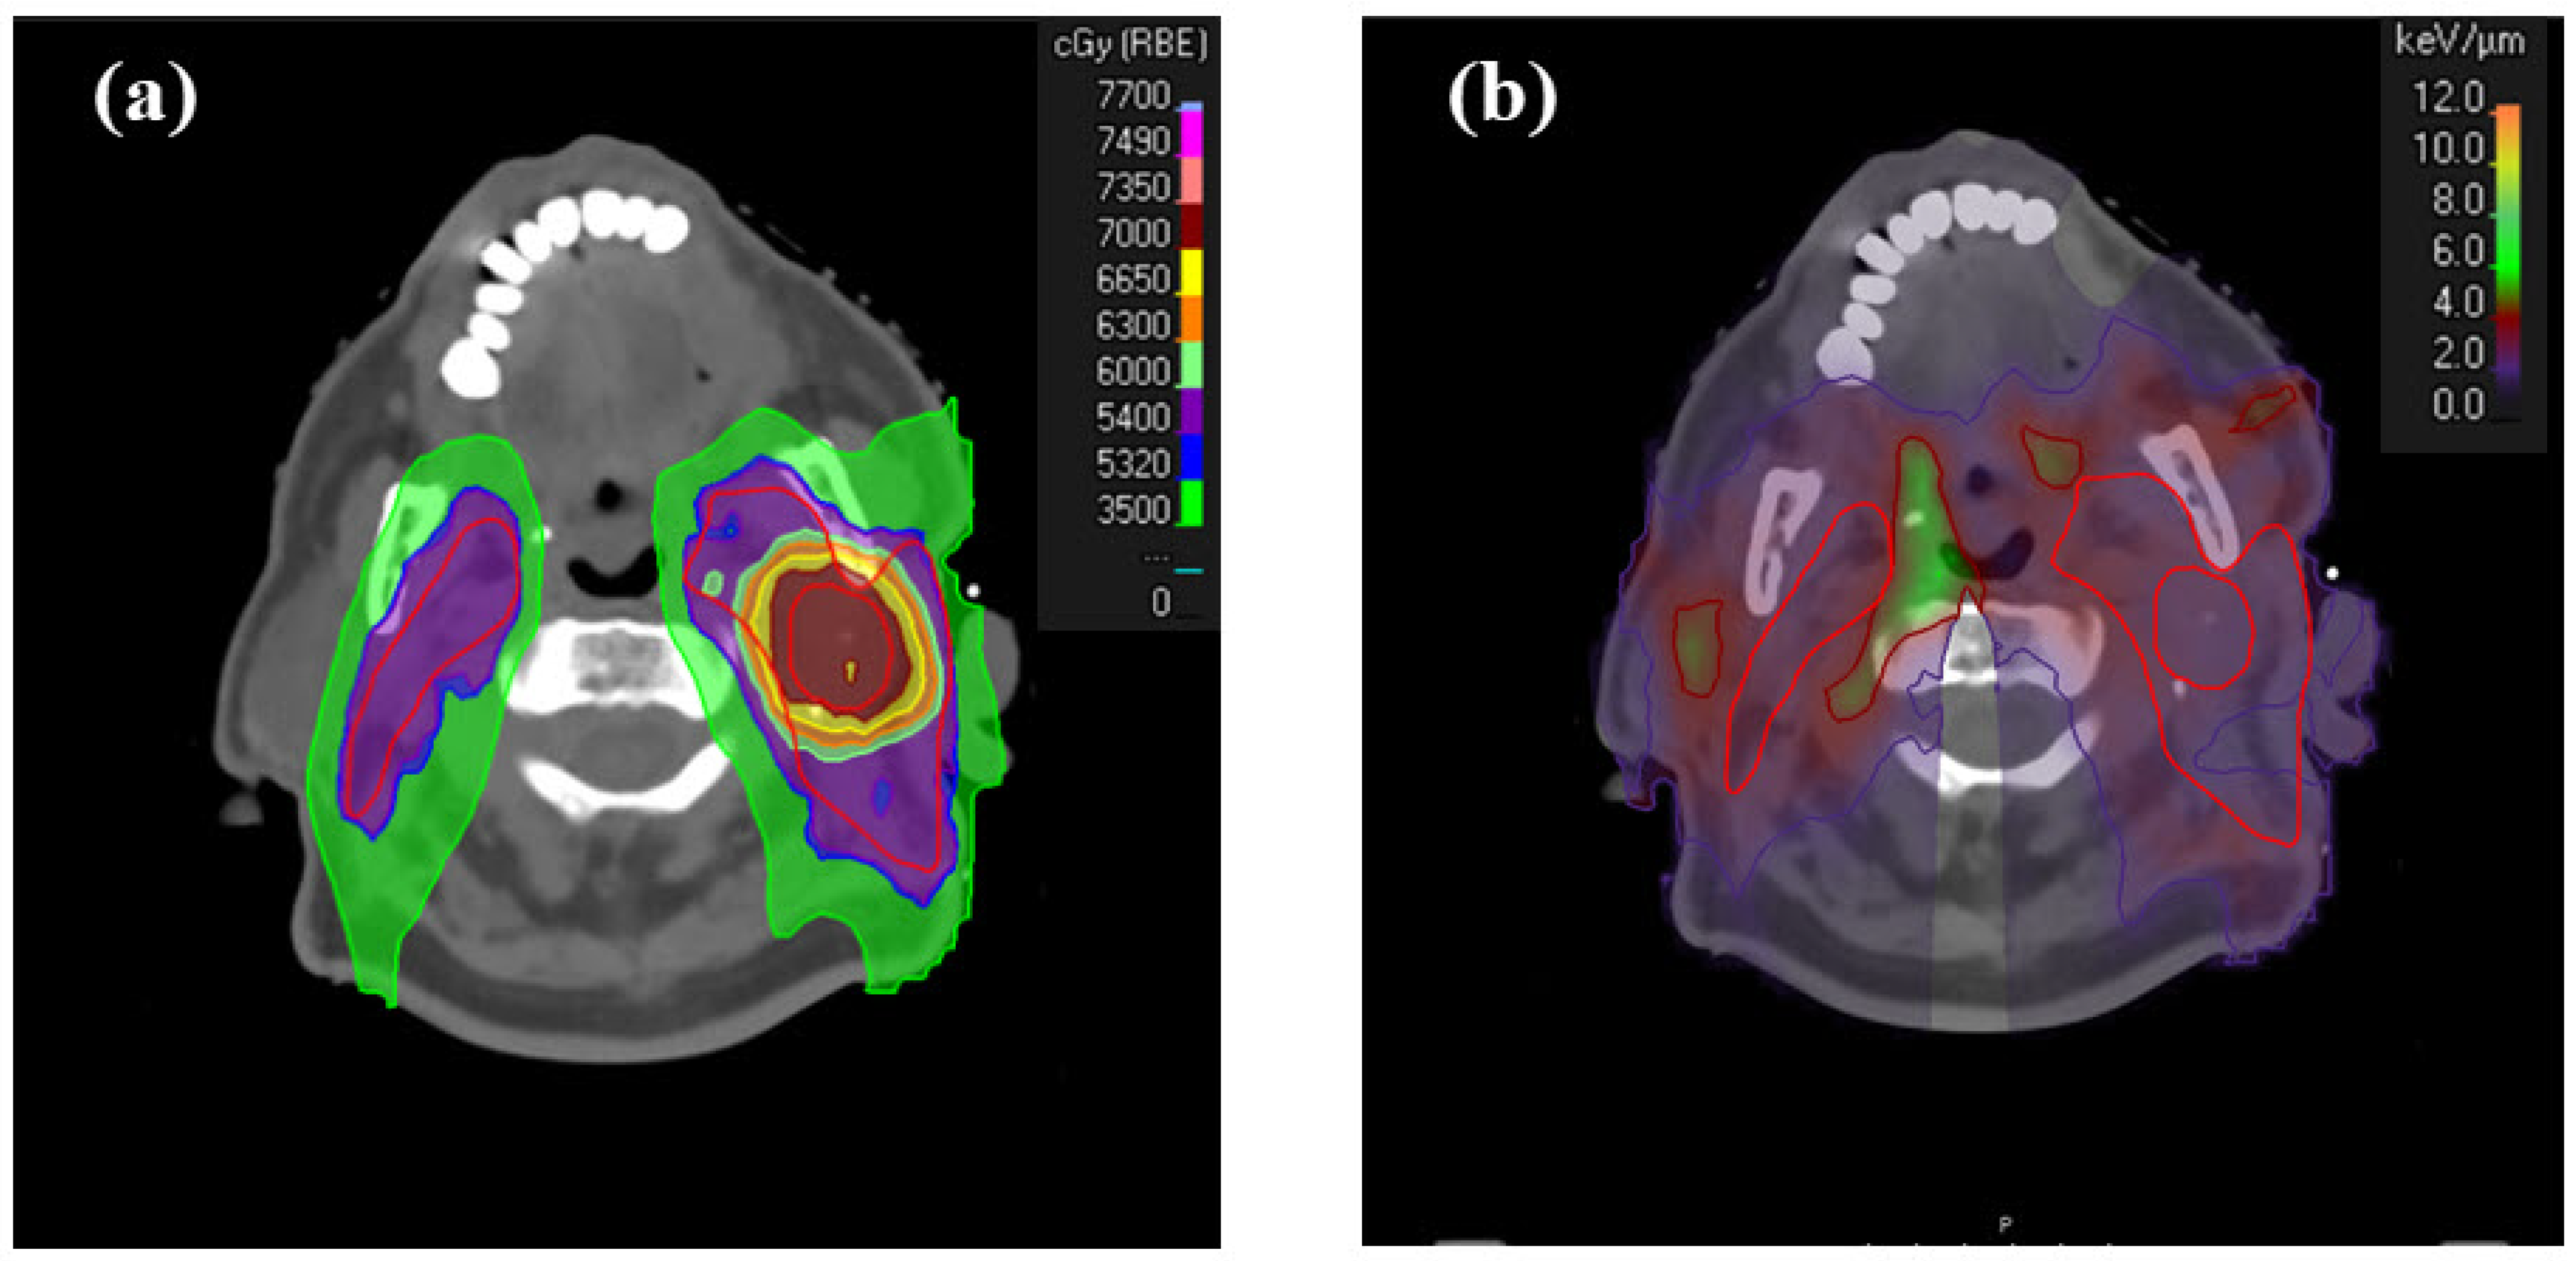

1. Introduction

2. Materials and Methods